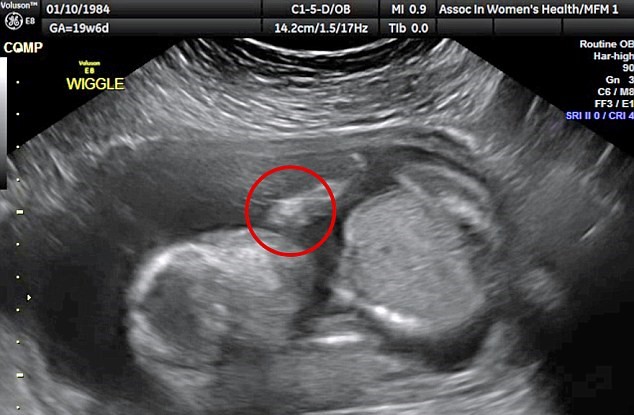

WICHITA – YOUTUBE Feto si prende a cazzotti in testa. Una coppia che vive a Wichita in Kansas è rimasta sorpresa nel vedere il feto del loro primo figlio che si prende a cazzotti in faccia. Almeno questo è quello che si vede nell’ecografia 3D pubblicata sul Daily Mail: il bambino appare molto irrequieto e sembra colpirsi con dei pugni sulla testa. Dave e Vanessa Watson sono rimasti di stucco nel vedere Edward James, questo il nome scelto per il pargolo, che si dà i pugni sul viso.

L’ecografia in questione è quella delle 20 settimane e risale allo scorso 26 gennaio. Vanessa, 32 anni , e Dave, 37, sono sposati da due anni e sono in attesa del loro primo figlio. Parlando della radiografia, Dave, un gestore di servizi per la ristorazione racconta: “E’ stato un vero choc. Stavamo guardando l’ecografia in tempo reale e improvvisamente è accaduto questo. L’infermiera si è messa a ridere e ci ha detto che non aveva mai visto niente del genere”.

A 20 settimane di età il feto misura, in genere, circa 26 centimetri. Il feto è già in grado di girarsi e di eseguire capriole.